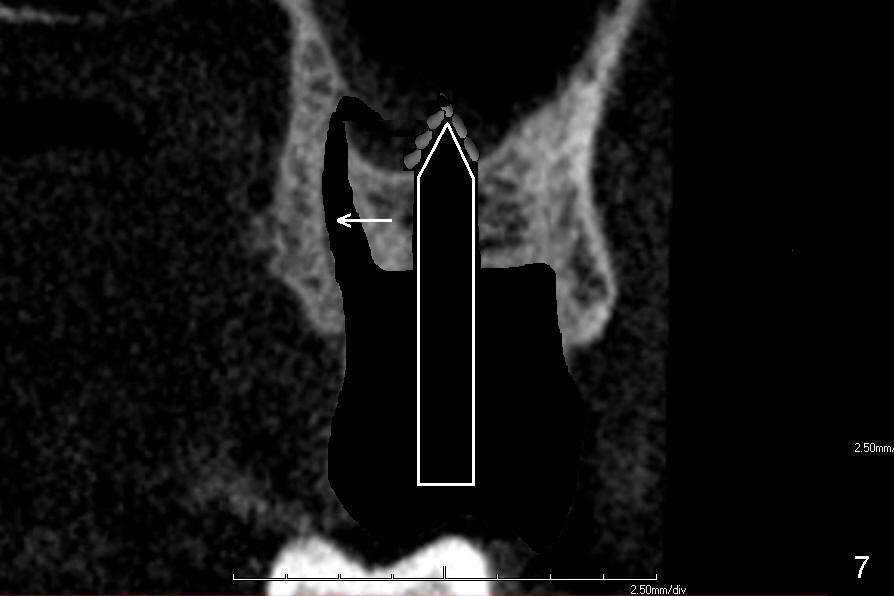

If the septum is small or destroyed by the infection, an implant will be placed in the palatal root (Fig.5), since it is the biggest among these 3 roots (Fig.2). The advantage is that the implant is longer than that placed in the septum (Fig.8). The drawback is that the implant is off center (Fig.5, as compared to that placed in the septum (Fig.8)). The implant placed in the palatal socket is relatively small in diameter. The whole socket will not be occupied by the implant. Collagen membrane will be used to help close the socket as well as bone graft.

If the septum is not so bad in size, osteotomes (RT series) will be used to expand it (to obliterate 3 sockets) and finish sinus lift to increase implant length if bone is not too hard to manipulate (Fig.6,7). Osteotomy is finished by using proper size and length of taps. Finally a large, but relatively short implant is placed in the septum (Fig.8). Arrowheads in Fig.6-8 indicate that as osteotomes are driven in sequentially (Fig.6,7 white box) and the implant is placed (Fig.8), bone segment may be moved palatally to obliterate the palatal socket gradually.